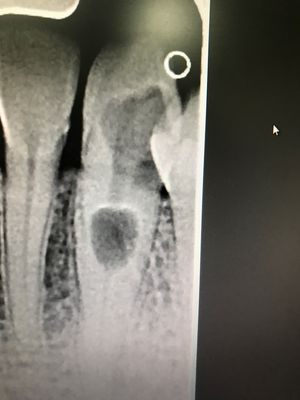

Holy tooth.

Tooth had massive decay causing the nerve to resorb inside out.